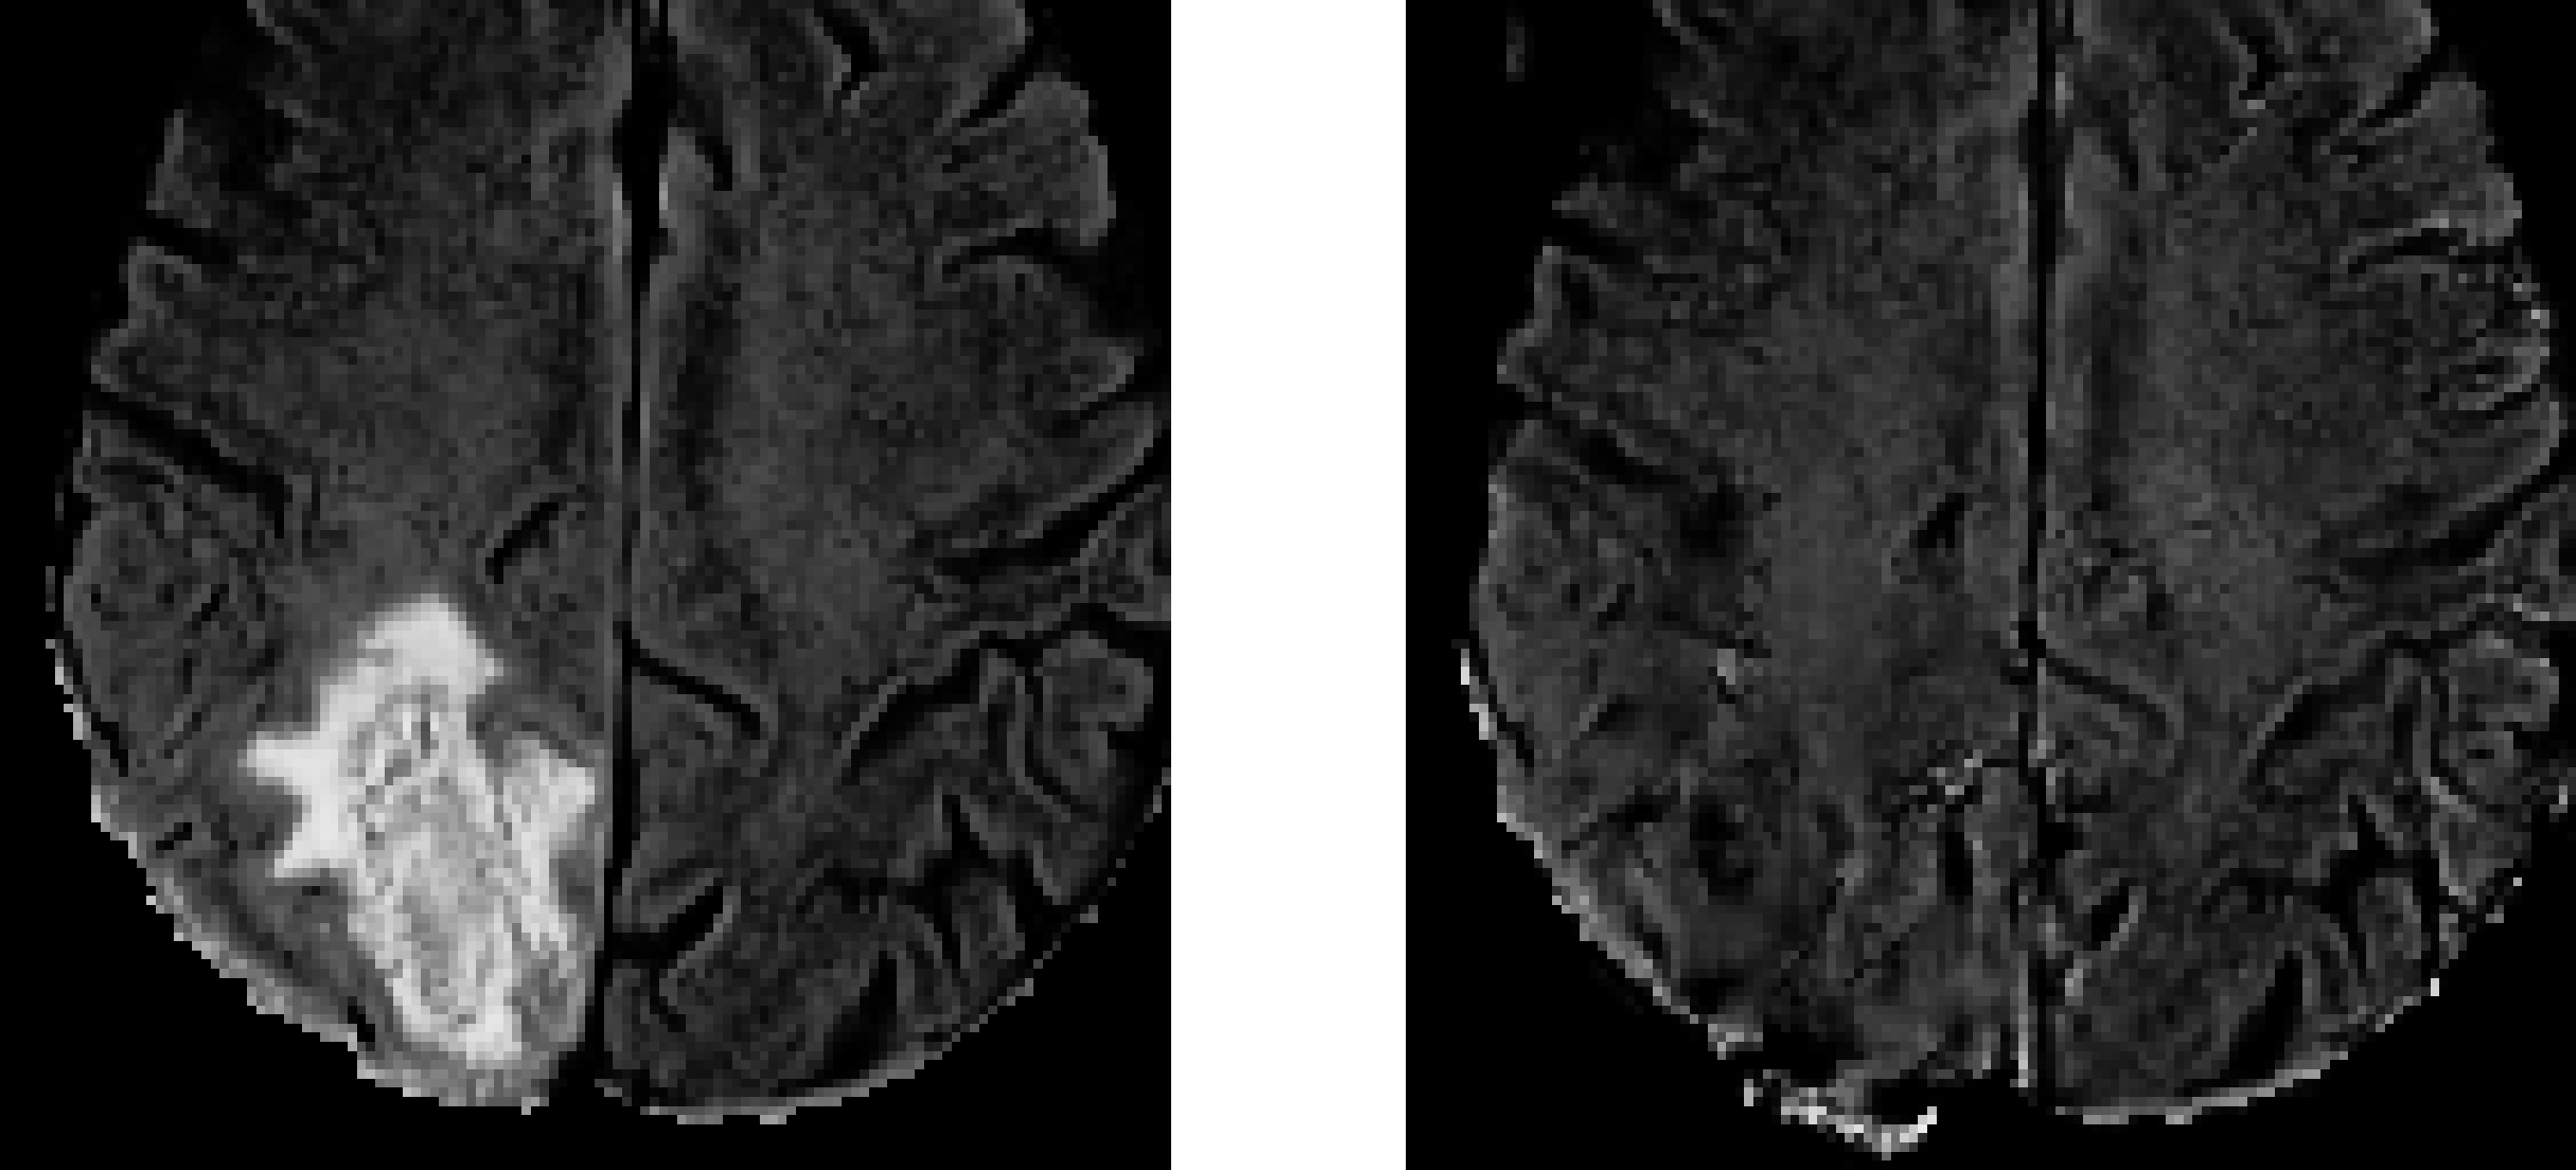

Examples of cancerous MR images and their generated non-cancerous variants are presented in Figure 5. Examples of cancerous MR images, their generated segmentations, and their true segmentations are visualized in Figure 6.

Refer to caption

(a) Example 1.

(b) Example 2.

Fig. 5: Examples of MR image FLAIR channel (left) and their generated non-cancerous variant (right).